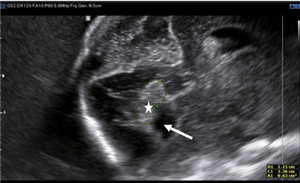

CLS: Siêu âm tim thai thông liên thất